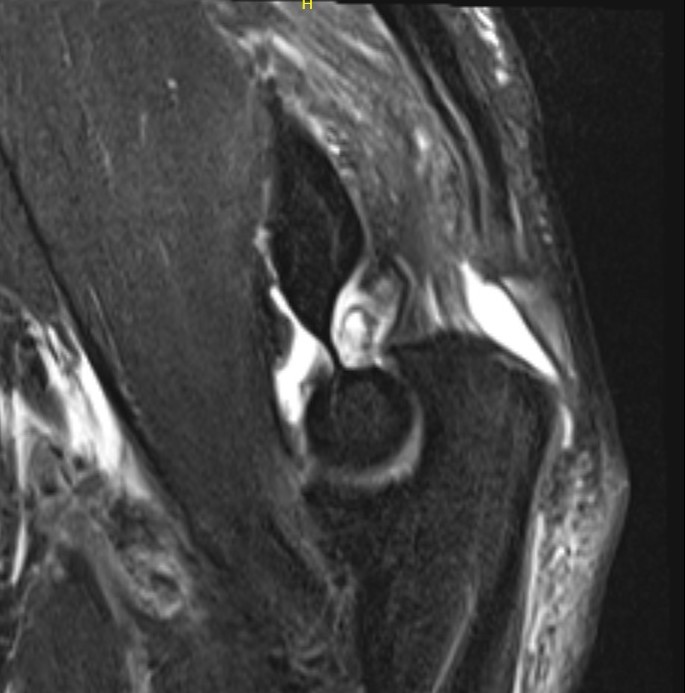

MRI